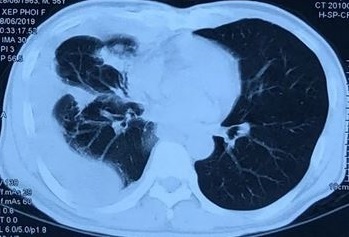

Sinh thiết tổn thương làm mô bệnh học, bệnh nhân nhận kết quả ung thư biểu mô tuyến biệt hóa vừa. Kết quả chụp cắt lớp vi tính ổ bụng cho thấy hình ảnh khối nhu mô gan hạ phân thùy V gan phải, kích thước 25x36 mm. Bệnh nhân được chẩn đoán ung thư đại tràng sigma di căn phổi, gan (giai đoạn IV).